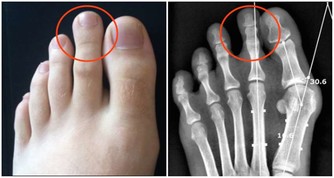

一個人一定要從年輕開始,保持你的標準體重。一旦胖了以後,想降下來就非常不容易了。

控制體重的關鍵在哪兒?

控制嘴、多動腿,人就是“死在嘴上,懶在腿上”。